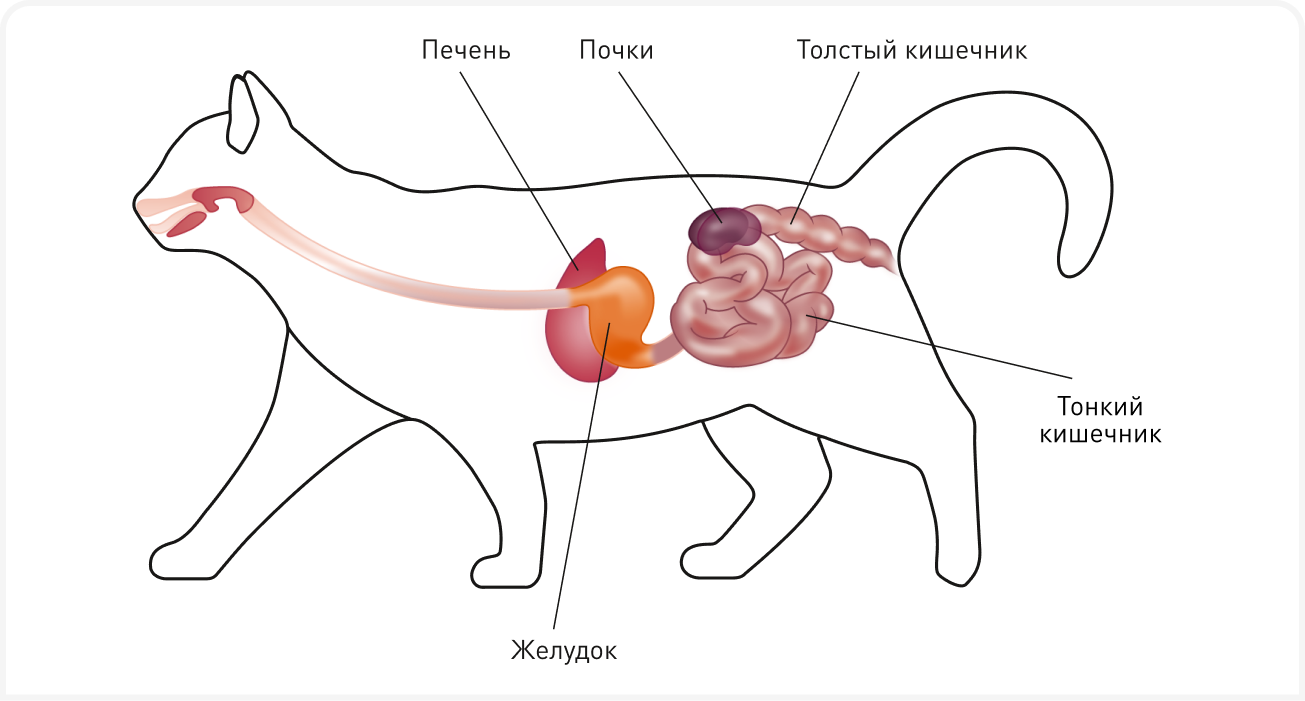

Растущий объем исследований подтверждает наличие у многих видов важной связи между кишечником и почками (так называемой оси кишечник — почки) (Рисунок 1). Обе системы значительно влияют друг на друга, что может иметь значительные клинические последствия. У кошек с хронической болезнью почек (ХБП) развивается дисбиоз, что подтверждает идею о том, что терапевтическое воздействие на кишечник может потенциально повышать продолжительность жизни и способствовать лечению сопутствующих заболеваний. В этой статье рассматривается современное понимание оси кишечник — почки и дается обзор доступных ветеринарным врачам стратегий оздоровления кишечного микробиома, что способствует снижению накопления опасных уремических токсинов, поступающих из кишечника.

Микробиом кишечника определяют как совокупность микроорганизмов, в основном бактерий. Эти микроорганизмы обитают в желудочно-кишечном тракте и образуют экосистему со сложным взаимодействием между собой и с хозяином. Кишечник кошек населяют триллионы кишечных бактерий из тысяч филотипов, имеющие обширные функциональные возможности. Этот широкий спектр микроорганизмов играет важную роль в поддержании здоровья хозяина, как за счет продуктов метаболизма бактерий, так и за счет влияния на экспрессию генов в кишечнике. Здоровая бактериальная микробиота и связь между хозяином и метаболитами бактерий жизненно важны для развития и поддержания здоровья иммунной системы, усвоения пищи, поддержания целостности кишечного барьера, синтеза питательных веществ (например, короткоцепочечных жирных кислот, витамина В12) и защиты от проникновения кишечных патогенов (1).

Индол и п-крезол, предшественники уремических токсинов, образуются при катаболизме белков микробиотой толстой кишки (4, 5). Индолы образуются в результате метаболизма триптофана пищи под действием триптофаназы кишечной микробиоты, например, микроорганизмов Escherichia coli (E. coli), Proteus vulgaris и Bacteroides spp. (Рисунок 2). П-крезол образуется в результате частичного расщепления тирозина и фенилаланина многими облигатными или факультативными анаэробами кишечника, включая микроорганизмы родов Bacteroides, Lactobacillus, Enterobacter, Bifidobacterium и Clostridium. Индол и п-крезол всасываются, а затем сульфируются в печени с образованием связанных с белками уремических токсинов IS и pCS соответственно. Эти токсины обычно выводятся почками, поэтому у пациентов с болезнью почек накапливаются в системном кровотоке. Выработке уремических токсинов, происходящих из толстого кишечника, дополнительно способствует дисбиоз, инициируя порочный круг (4, 5). Нарушение усвоения белка в тонком кишечнике при ХБП увеличивает содержание белкового субстрата в просвете кишечника, что способствует размножению протеолитических бактерий, продуцирующих предшественники уремического токсина. Определенную роль также может играть запор, сопровождающийся длительной задержкой каловых масс в толстой кишке; у пациентов с ХБП, страдающих запорами, уровень уремических токсинов выше, чем при нормальной балльной оценке фекалий (6).